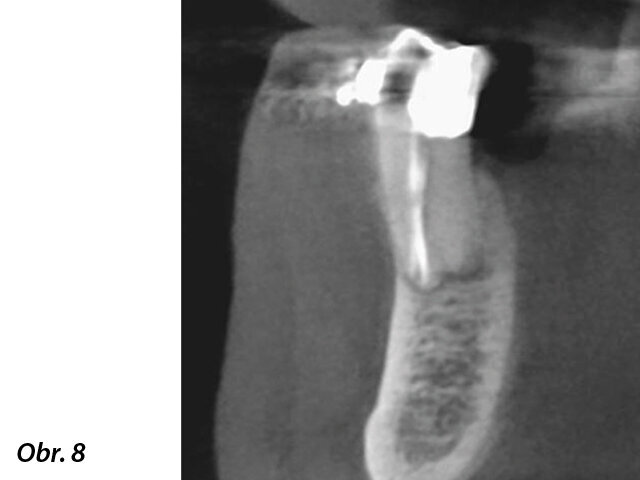

Situace byla zcela odlišná u dolního premoláru na obr. 7–9, kde si při absenci radiologických znaků léze, a i přes zdánlivě správný endodontický přístup jiného kolegy, pacient stěžoval na perzistentní bolest, která byla jak spontánní, tak vyvolaná poklepem. V tomto případě, kdy se zdála být předchozí léčba kořenových kanálků dobrá, by se jako vhodný mohl nabízet chirurgický přístup, který by v takovém případě mohl zajistit vyšší míru úspěšnosti než revize endodontického ošetření. Vzhledem k diagnostickým pochybnostem bylo rozhodnuto zhotovit 3D snímek, který odhalil endodontickou lézi způsobenou neošetřeným lingválním kanálkem. Tato správná diagnóza nám tedy umožnila provést selektivní intervenci na zbylé pulpě vedoucí k úspěšné léčbě neošetřeného kanálku.